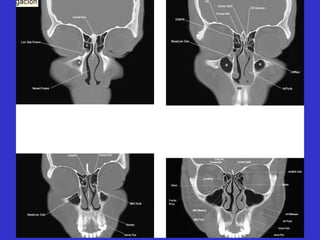

Este documento describe las diferentes proyecciones radiográficas utilizadas para examinar los senos paranasales, incluyendo las proyecciones básicas de Caldwell, Waters lateral y las proyecciones especiales como Hirtz y Waters mentonasal. También describe las diferentes estructuras anatómicas que componen el complejo ostiomeatal anterior y posterior de los senos paranasales.